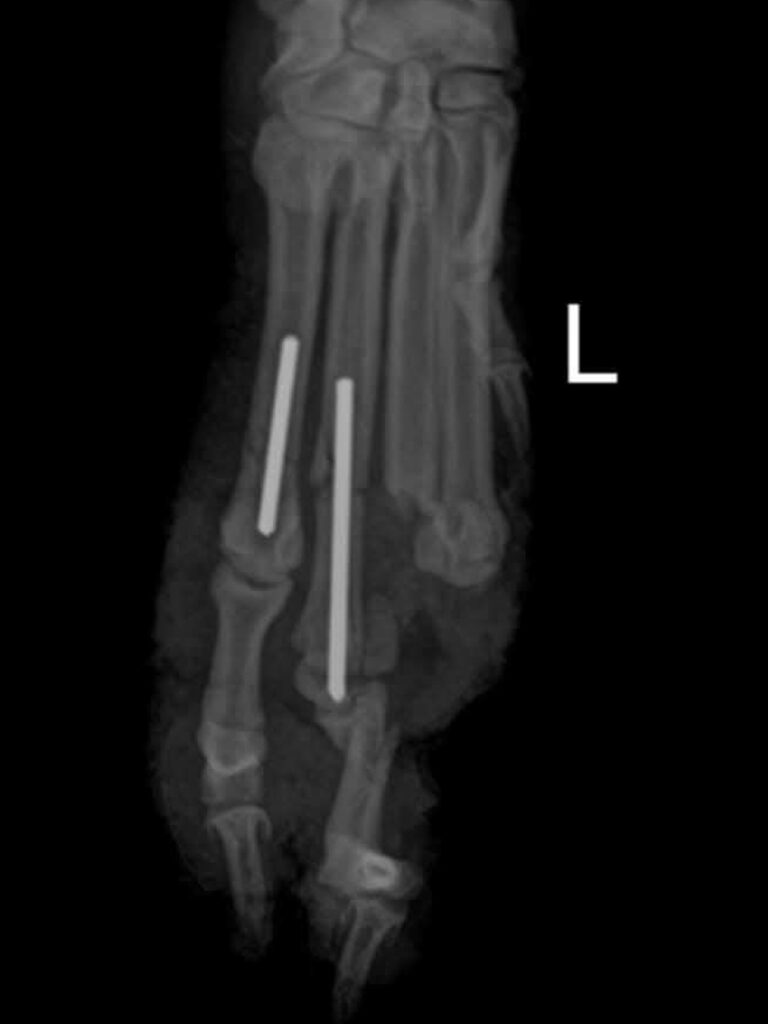

Ein paar Leute vor Ort haben sich zusammengetan und ihn zum Tierarzt gebracht zur Erstversorgung. Als das Hochwasser kam, evakuierten sie ihn und brachten ihn in Sicherheit.

Was übrig bleibt, sind hohe Rechnungen beim Tierarzt und ein Hund, der nach all dem Ärger und Leid nicht mehr zurück auf die Straße kann. Die Leute wandten sich an uns und baten um Hilfe. Wir versprachen unser Möglichstes zu tun, um ihm zu helfen. Voraussichtlich benötigt er weitere ärztliche Versorgung, um vollends zu genesen.